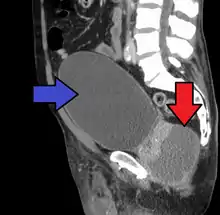

Abscess of the prostate (red arrow) resulting in urinary retention (blue arrow)

Severely ill patients may need hospitalization, while nontoxic patients can be treated at home with bed rest, analgesics, stool softeners, and hydration. Men with acute prostatitis complicated by urinary retention are best managed with a suprapubic catheter or intermittent catheterization. Lack of clinical response to antibiotics should raise the suspicion of an abscess and prompt an imaging study such as a transrectal ultrasound (TRUS).[7]